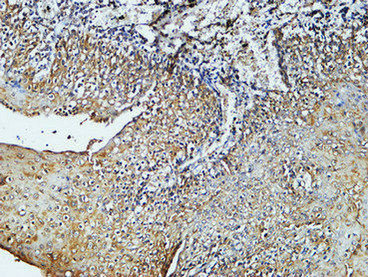

Immunohistochemistry analysis of paraffin-embedded Human stomach tissue using CD4 antibody.High-pressure and temperature Sodium Citrate pH 6.0 was used for antigen retrieval.Negative control was used by secondary antibody only.

Immunohistochemical analysis of paraffin-embedded Human tonsils using CD4 antibody.High-pressure and temperature Sodium Citrate pH 6.0 was used for antigen retrieval.Negative control was used by secondary antibody only.

Immunohistochemistry analysis of paraffin-embedded mouse brain tissue using CD4 antibody. High-pressure and temperature Sodium Citrate pH 6.0 was used for antigen retrieval. Negative control was used by secondary antibody only.

Immunohistochemistry analysis of paraffin-embedded Human Amygdala using CD4 antibody.High-pressure and temperature Tris-EDTA pH 8.0 was used for antigen retrieval.